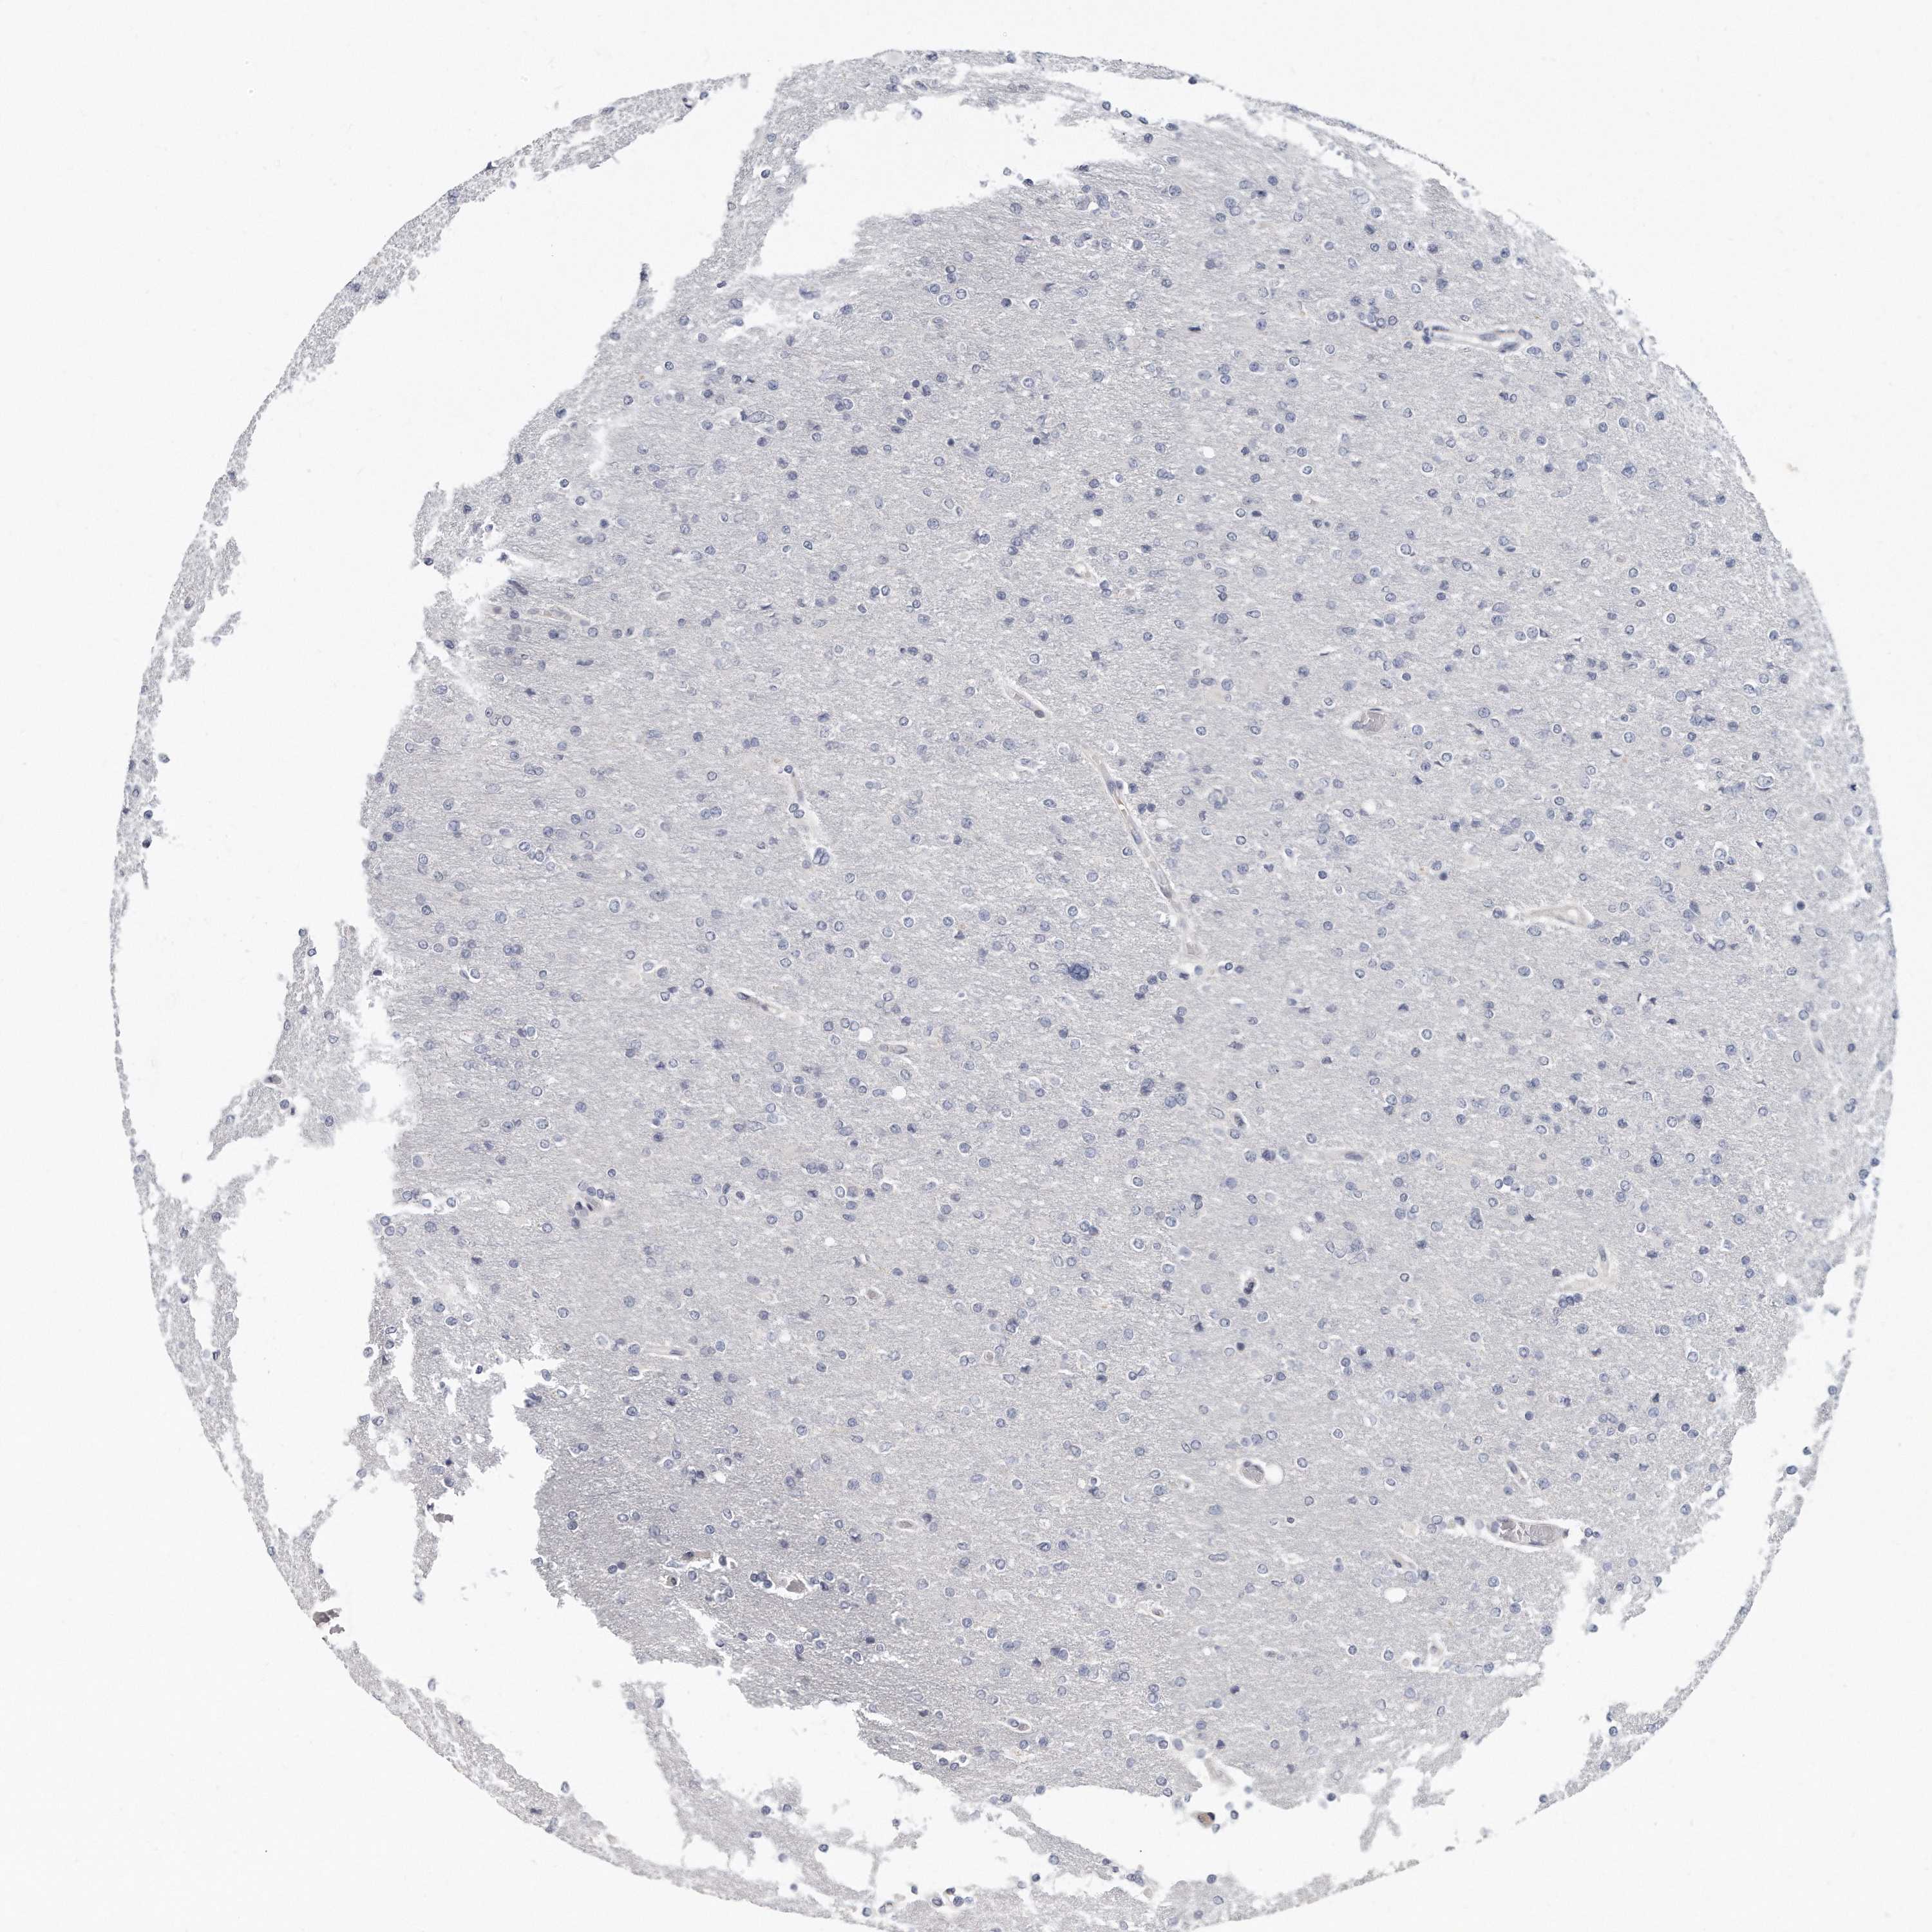

GLIOMA - Protein expressioni

A mouse-over function shows sample information and annotation data. Click on an image to view it in a full screen mode. Samples can be filtered based on level of antibody staining by selecting one or several of the following categories: high, medium, low and not detected. The assay and annotation is described here.

Note that samples used for immunohistochemistry by the Human Protein Atlas do not correspond to samples in the TCGA dataset.

Antibody stainingi

Antibody staining in the annotated cell types in the current human tissue is reported as not detected, low, medium, or high, based on conventional immunohistochemistry profiling in selected tissues. This score is based on the combination of the staining intensity and fraction of stained cells.

Each image is clickable and will lead to virtual microscopy that enables deeper exploration of all samples and also displays staining intensity scores, fraction scores and subcellular localization as well as patient and tissue information for each sample.

Antibody HPA028152

Staining

High

Medium

Low

Not detected

Intensity

Strong

Moderate

Weak

Negative

Quantity

>75%

75%-25%

<25%

None

Location

Nuclear

Cytoplasmic/membranous

Cytoplasmic/membranous,nuclear

Glioma, malignant, High grade

Glioma, malignant, Low grade

Glioblastoma, NOS